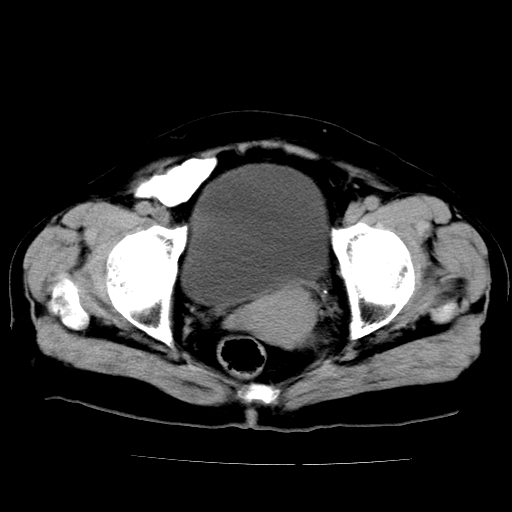

女,73岁,阴道流血一周。

宫颈不规则增大;结合临床考虑宫颈癌。建议作mri检查

1\\老年妇女突发阴道流血,常见病考虑宫颈癌.本病例宫颈部显示形态不规则,密度欠均匀,支持考虑宫 颈癌,建议mri 或阴道超声坚持

2\\但是盆腔两侧尚未见到明显肿大淋巴结等转移征象

宫颈不规则增大,左后方可见结节状突起.支持宫颈癌.

宫颈壁明显增厚,左侧为甚,宫颈癌待排,建议宫颈涂片细胞学检查。

宫颈不规则增大,周围脂肪间隙毛糙,结合临床考虑宫颈癌,盆腔内未见肿大淋巴结。